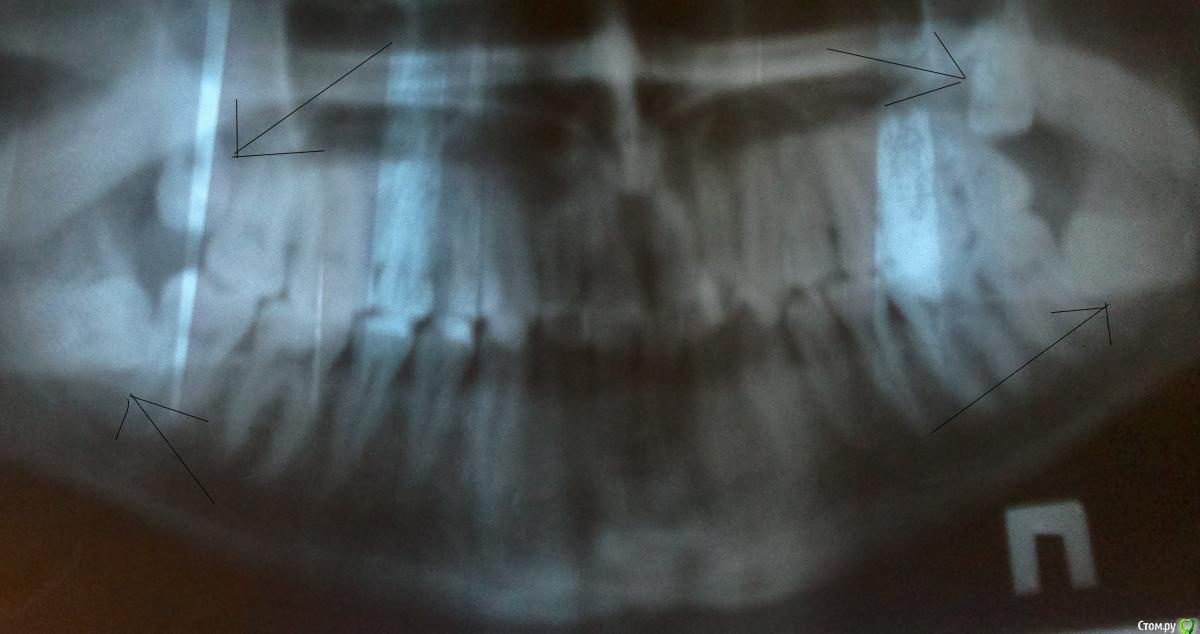

Собственно вопрос, прошу прощения за вступление. Зубы мудрости у меня имеются в рукаве, вернее в челюсти. Верхние еще ничего, левый неделю назад площадку стал образовывать, говорит утром:" воды, воды, хозяин, а то кальция много, закальцируюсь", правый будет повторять судьбу брата через 3-4 недели, место-то освободилось, шустрят мальцы. Лежали они хорошо, на снимке видно. А вот нижние лежат так, что их удалят с большой радостью 100% хирургов и процентов 95-99 ортодонтов.

Снимок панорамный сделан до начала лечения, но нижняя челюсть только резцы поменялись и клык разворачивается на боевую позицию. Верхние-то притянулись мал-мала.